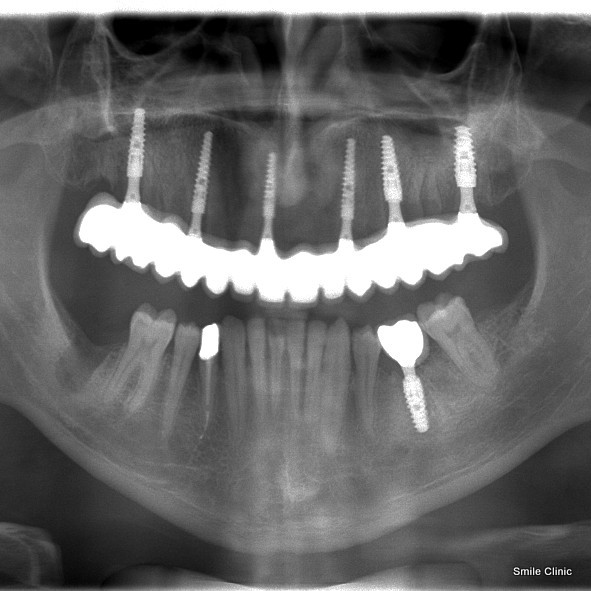

As you can see in the X-ray, on the 1st visit, 6 dental implants were placed to support 14 crowns as a bridge, and 2 more visits were needed to complete the treatment at the end of the year.